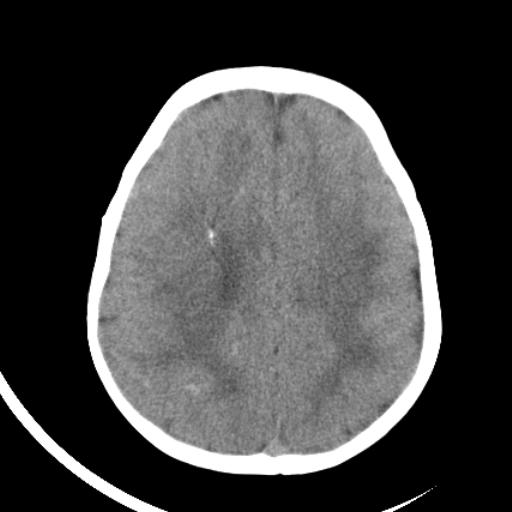

双侧脑室前后角周围白质片状低密度影,双侧侧脑室旁、双顶叶皮层及皮层下多个小原点状钙化灶,不除外torch感染。右顶叶脑回似乎较对侧大,建议mri检查以除外脑发育异常。

考虑:1、巨脑回畸形(皮质明显增厚+脑回明显增宽+白质减少)。

2、torch综合征(室管膜下钙化+白质内及皮髓质交界处多发钙化)。